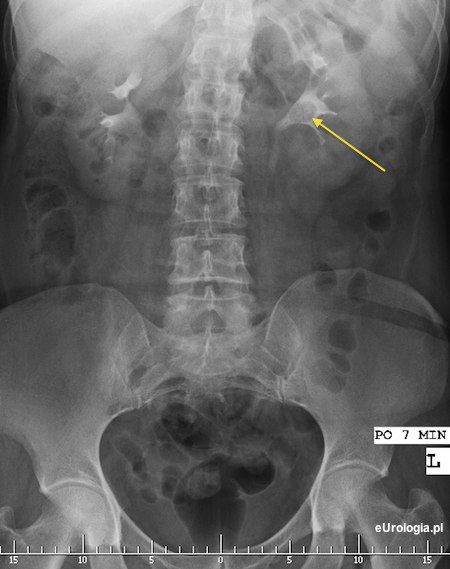

Fot. Złóg 17 mm w miedniczce nerkowej.

Nie znamy szczegółów istotnych przy kwalifikacji do PCNL więc nasze rozważania będą teoretyczne. U większości pacjentów z czterema złogami wielkości 10 - 14 mm leczeniem z wyboru byłaby przezskórna nefrolitotrypsja czyli PCNL. W razie niedoszczętnego usunięcia złogów możliwe jest uzupełnienie tej metody o litotrypsję zewnątrzustrojową falą uderzeniową. Zadaje Pan pytanie, czy nie lepiej jest wykonać ESWL ze względu na dolegliwości bólowe. Nie wiemy jaka jest przyczyna bólu - istotne jest jak usytuowane są złogi w układzie kielichowo - miedniczkowym i czy powodują one zaburzenia odpływu moczu. W razie silnych dolegliwości bólowych możliwe jest odbarczenie nerki cewnikiem JJ lub nefrostomią. ESWL przy tak dużych i licznych złogach wiąże się z dużym ryzykiem powikłań w postaci drogi kamiczej - steinstrasse. PCNL jest zabiegiem wiążącym się z ryzykiem powikłań więc jest to metoda, która nie jest wykonywana w trybie jednodniowym. Więcej informacji na temat ESWL i PCNL znajdzie Pan w odpowiednich działach naszego serwisu.